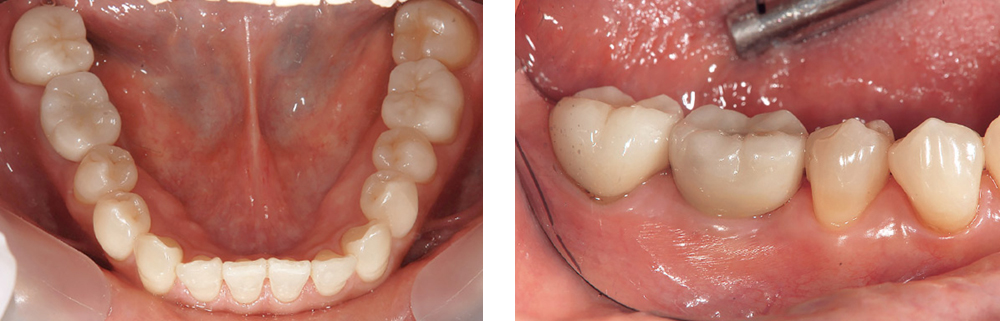

図9 初診時口腔内写真およびパノラマX線写真

④⑤⑥⑦のブリッジを装着していたが、歯根破折のため抜歯になりインプラント希望で当院に紹介。骨幅・骨高径および角化粘膜ともに十分にあるため、同部位に2本のSPIインプラントを一回法で埋入することとした。

図14 最終補綴装着時の口腔内写真およびパノラマX線写真

本症例では、CAD/CAM Co-Cr フレームを作製し、ポーセレンを築盛したPFMによる上部構造を装着した。

図15 1年経過後